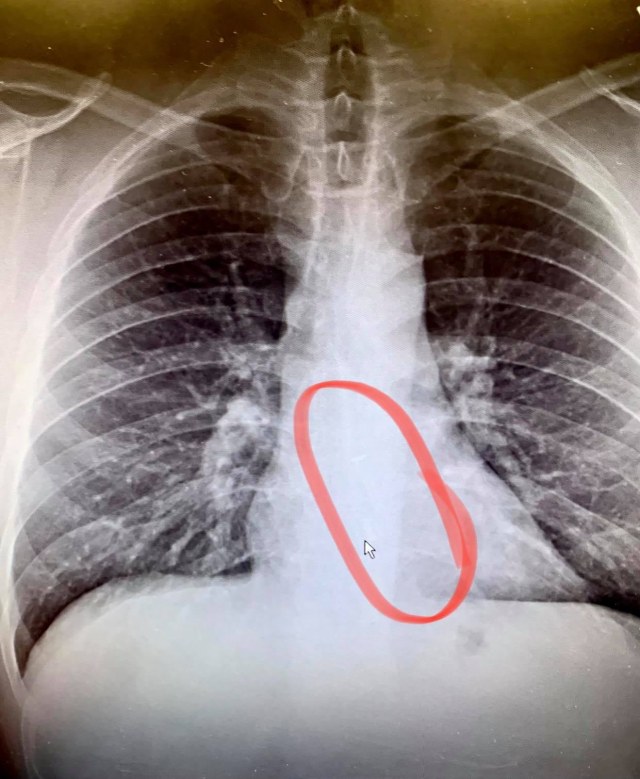

Ketika sampai di klinik, Gauthier melakukan pemeriksaan X-ray. Ternyata, AirPods tersebut memang ada dan nyangkut di bagian bawah kerongkongan.

"Dia (petugas klinik) berkata, 'Baiklah, kita akan menjalani X-ray,' Anda tahu, sebagai tindakan pencegahan, dan lihatlah, dia kembali ke kamar, dan raut wajahnya tak ternilai harganya," kata Gauthier.